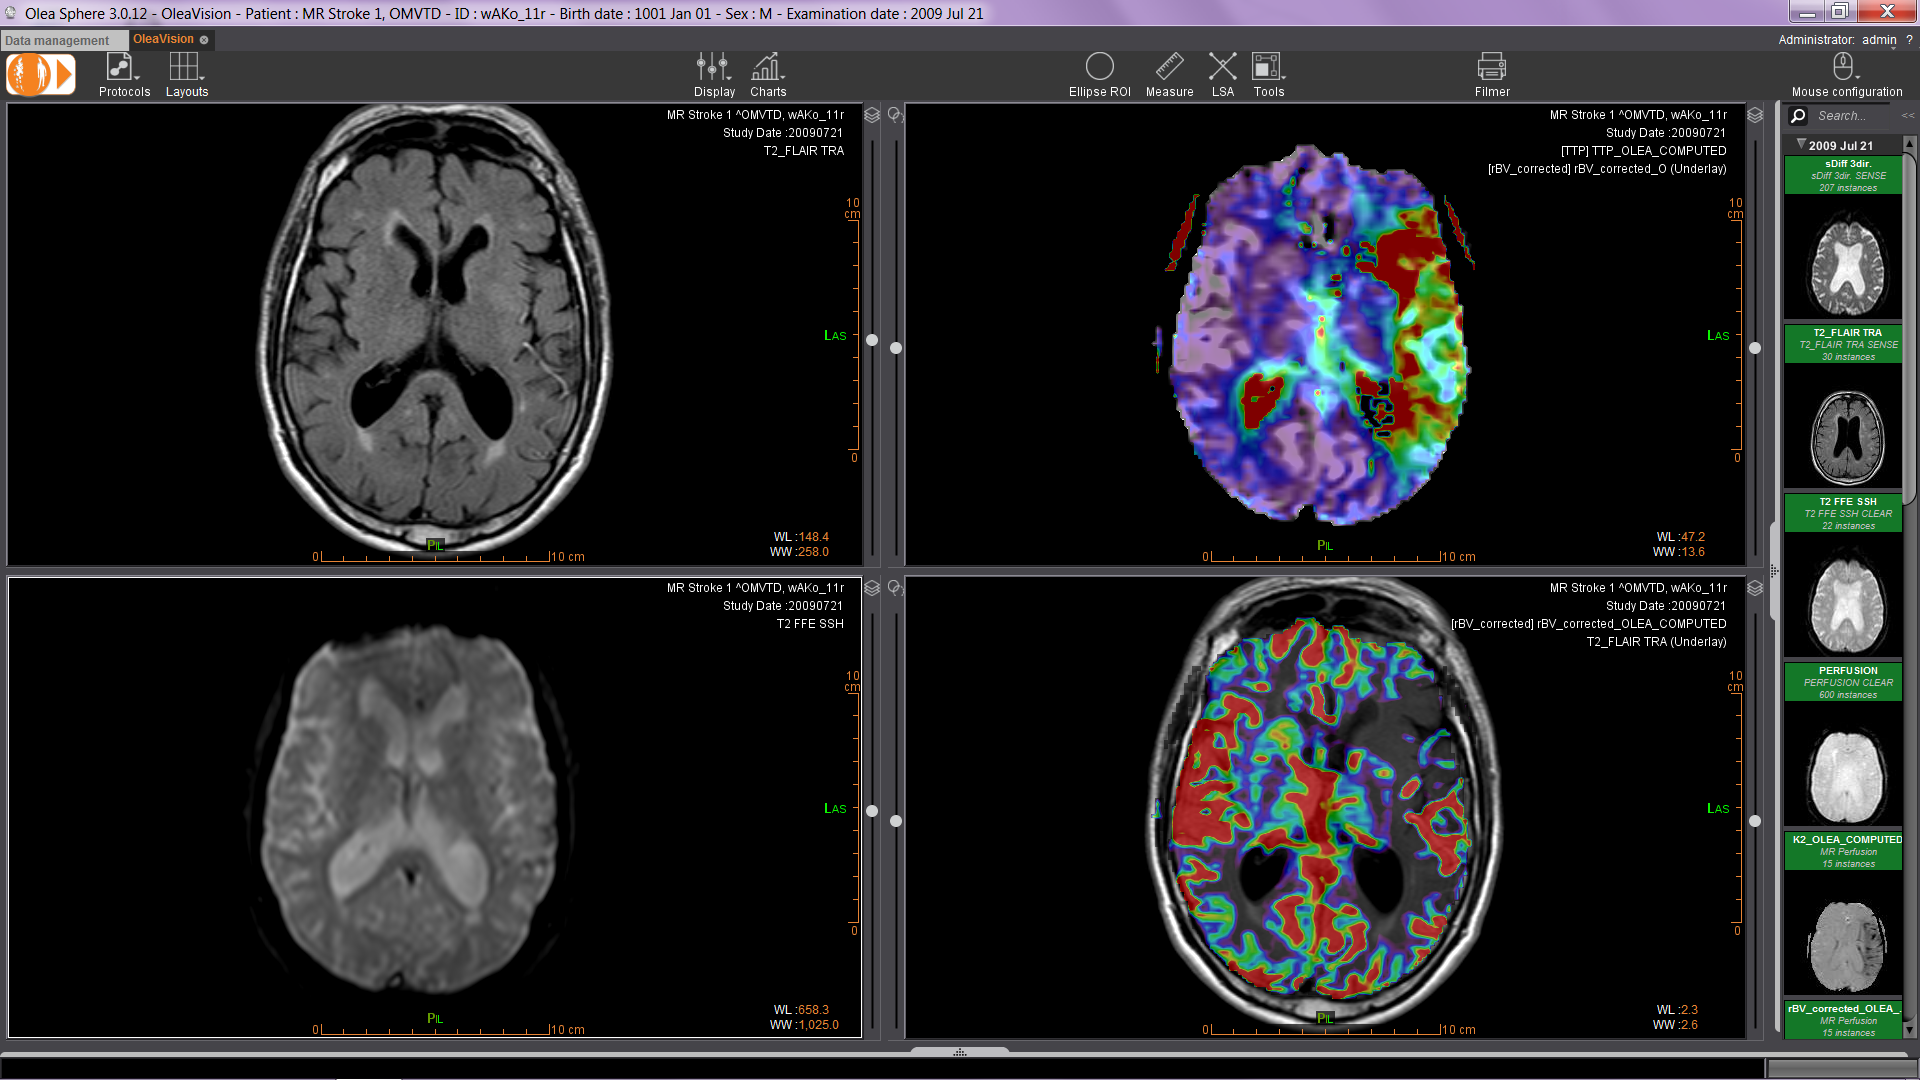

Olea Medical, spoločnosť Canon Medical Systems Corporation, je poskytovateľom inovatívnych riešení pre spracovanie obrazu MR a CT. Olea Sphere je automatizované riešenie pre následné spracovanie MRI a CT skenov, umožňujúce rýchle vyhodnotenie mnohých patológií. Olea Sphere používa viac ako 200 popredných inštitúcií na celom svete pre klinické aj výskumné účely.